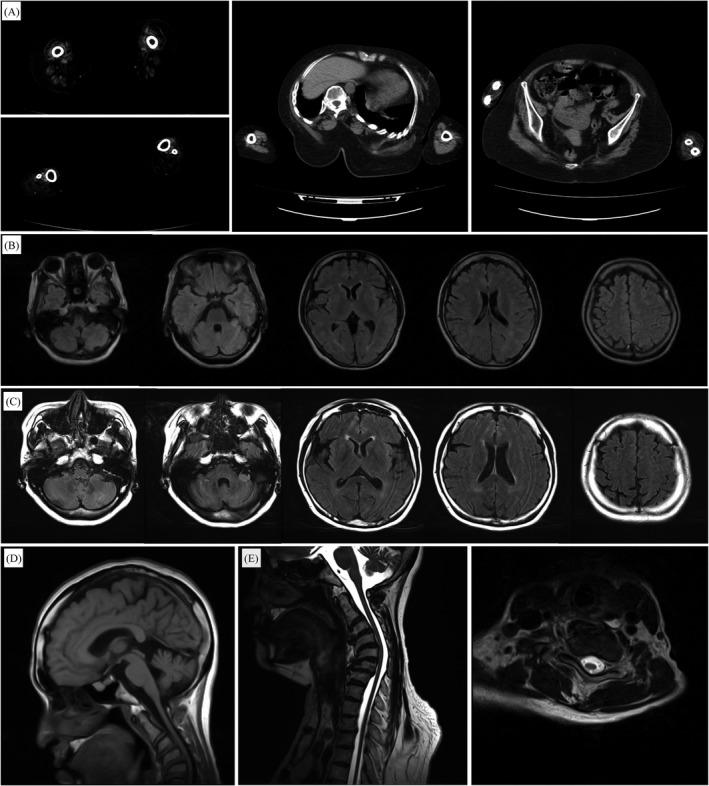

We identified de novo POLR3B heterozygous missense mutations in two patients. These patients presented with early-onset demyelinating sensorimotor neuropathy without ataxia, spasticity, or cognitive impairment. Patient 1 showed mild cerebellar atrophy and spinal cord atrophy on magnetic resonance imaging and eventually died of respiratory failure in her 50s. We classified these mutations as pathogenic based on segregation studies, comparison with control database, and in silico analysis.

我们在两名患者中发现了新生 POLR3B 杂合错义突变。这些患者表现为早发性脱髓鞘感觉运动神经病,无共济失调、痉挛或认知障碍。患者 1 的磁共振成像显示轻度小脑萎缩和脊髓萎缩,最终在 50 多岁时因呼吸衰竭而死亡。我们基于分离研究、与对照数据库的比较以及计算机模拟分析将这些突变归类为致病性突变。